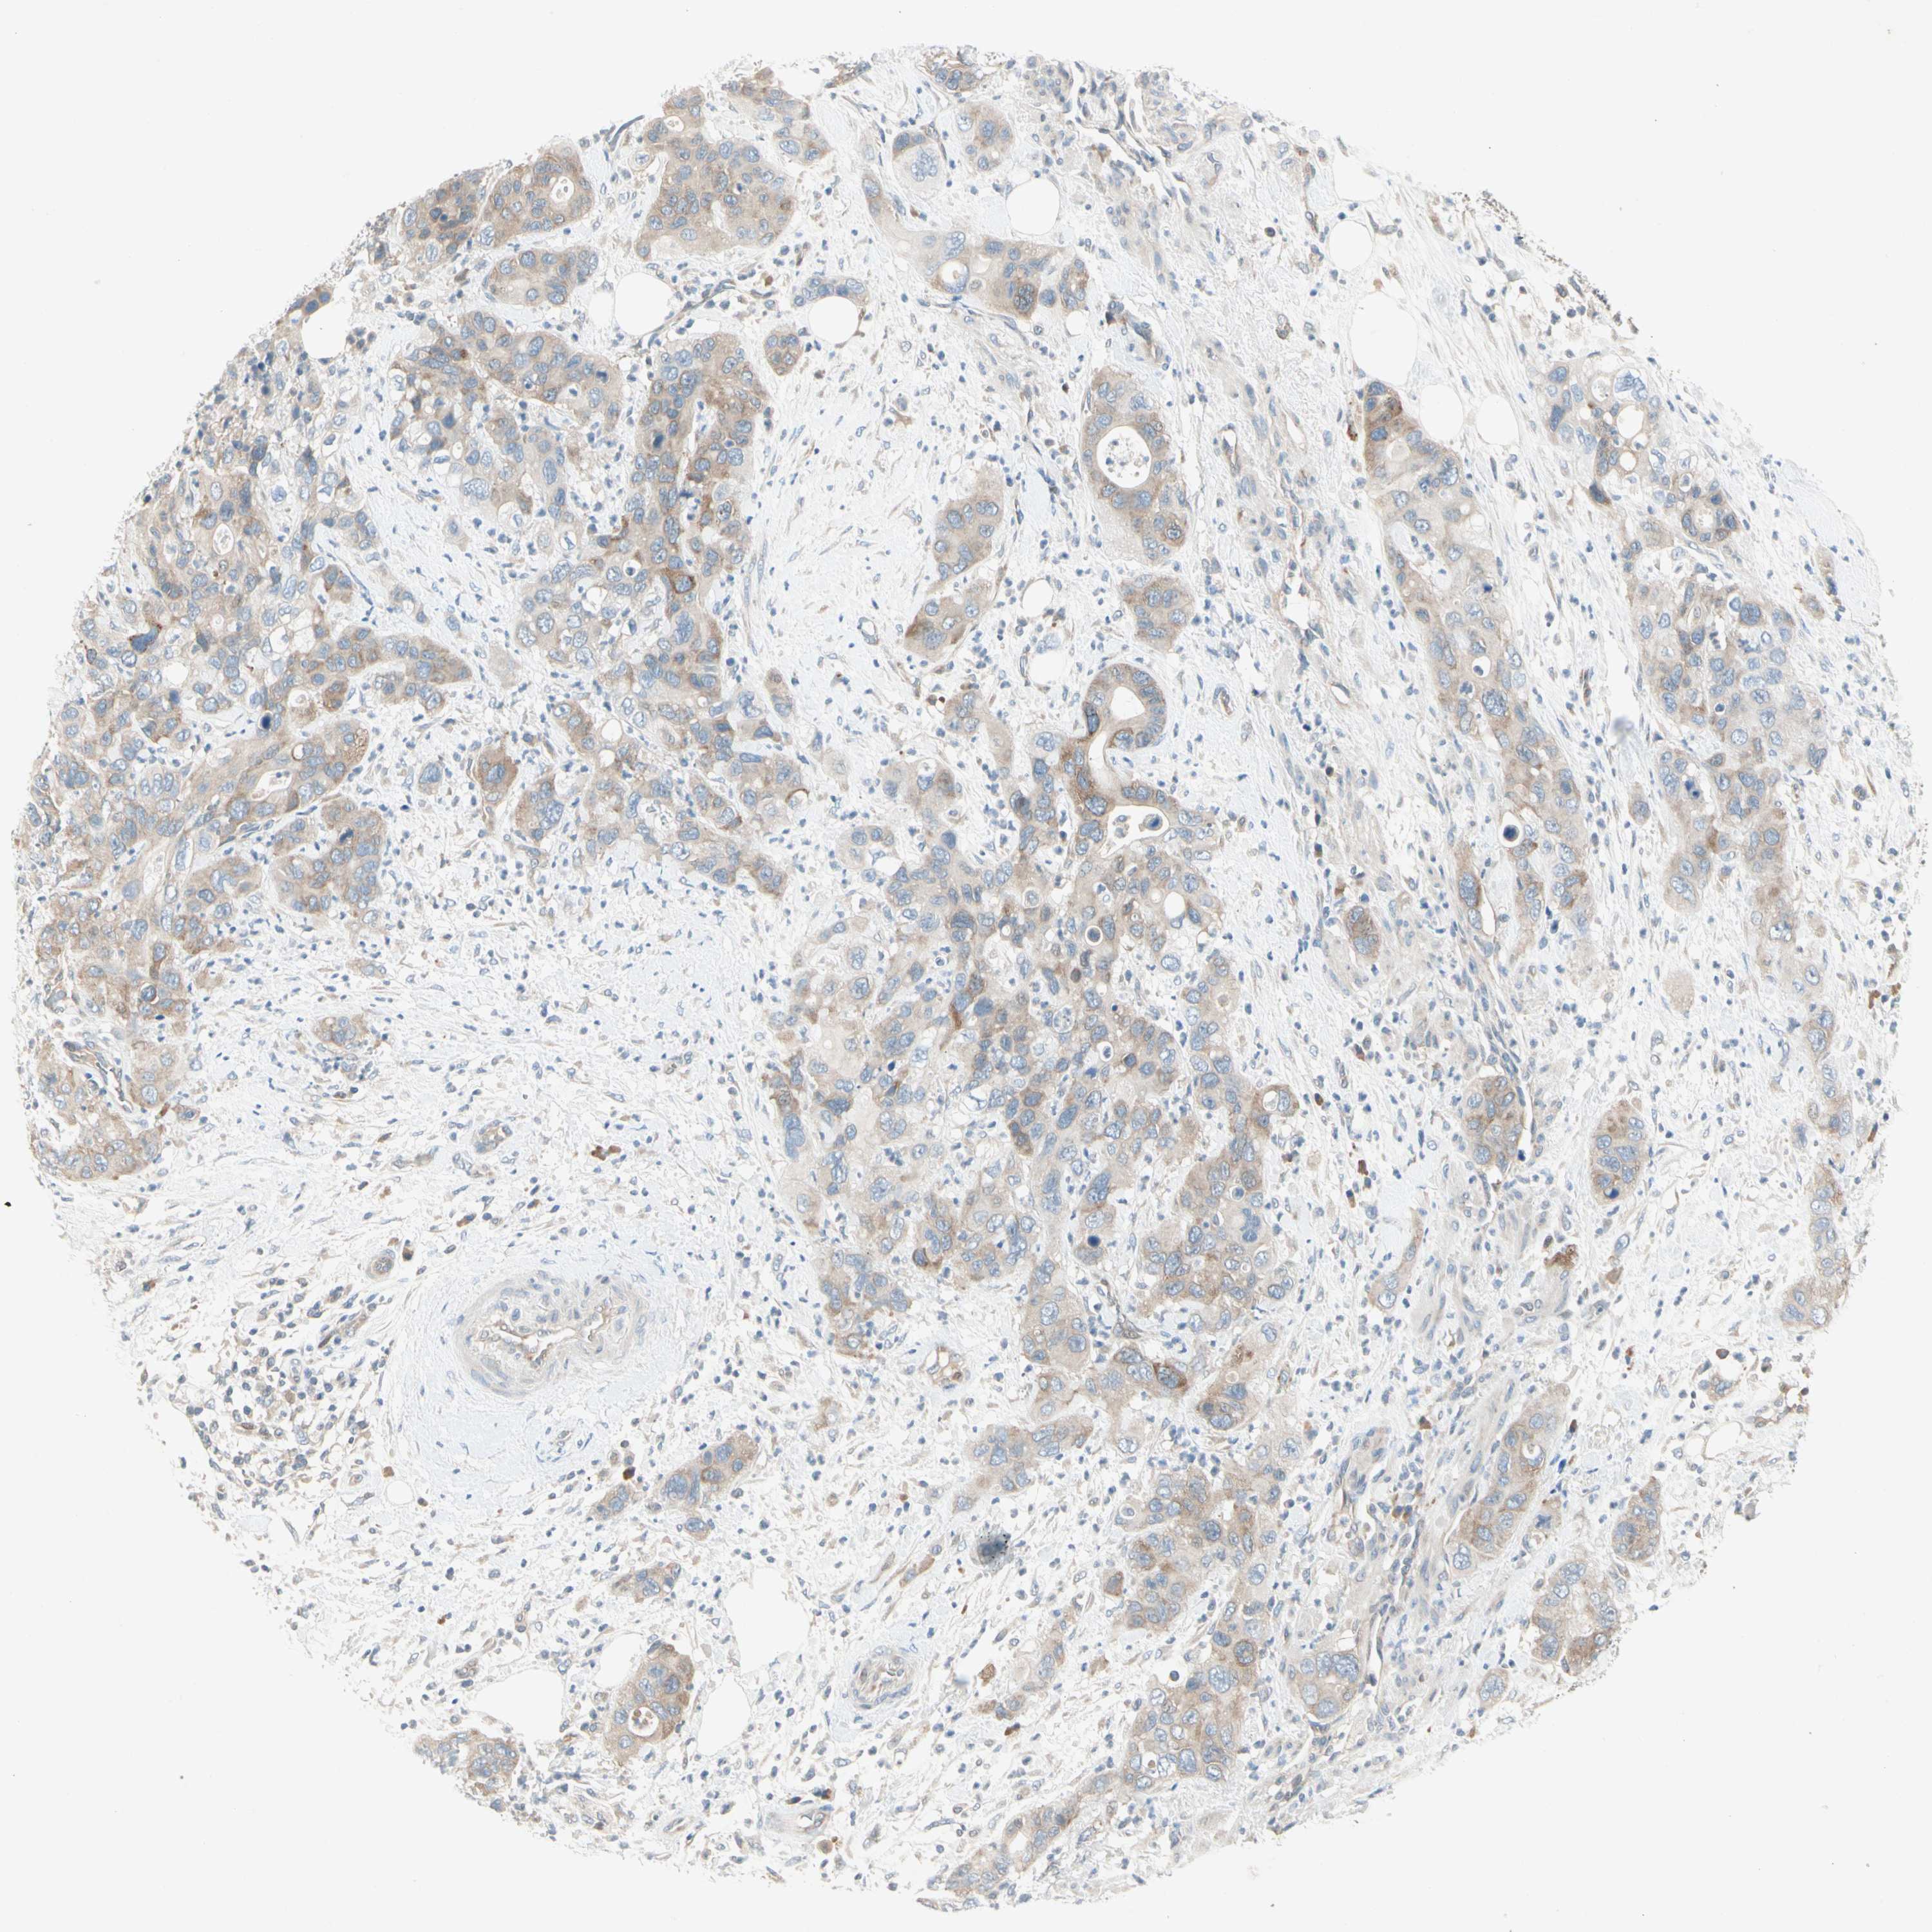

PANCREATIC CANCER - Protein expressioni

A mouse-over function shows sample information and annotation data. Click on an image to view it in a full screen mode. Samples can be filtered based on level of antibody staining by selecting one or several of the following categories: high, medium, low and not detected. The assay and annotation is described here.

Note that samples used for immunohistochemistry by the Human Protein Atlas do not correspond to samples in the TCGA dataset.

Antibody stainingi

Antibody staining in the annotated cell types in the current human tissue is reported as not detected, low, medium, or high, based on conventional immunohistochemistry profiling in selected tissues. This score is based on the combination of the staining intensity and fraction of stained cells.

Each image is clickable and will lead to virtual microscopy that enables deeper exploration of all samples and also displays staining intensity scores, fraction scores and subcellular localization as well as patient and tissue information for each sample.

Antibody HPA005823

Antibody HPA029560

Antibody CAB007779

Staining

High

Medium

Low

Not detected

Intensity

Strong

Moderate

Weak

Negative

Quantity

>75%

75%-25%

<25%

None

Location

Nuclear

Cytoplasmic/membranous

Cytoplasmic/membranous,nuclear

Adenocarcinoma, NOS